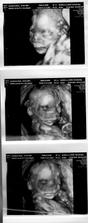

27.6. nedela - 3D ultrazvuk v HC, vsetko je ok, potvrdeny chlapec, nadherny zazitok

16.9. stvrtok - 4D ultrazvuk - Banovce nad Bebravou, MUDr. Baskova - vsetko ok, potvrdeny na 300% chlapec, 32tt+1 ale podla utz 32+5, vaha je cca 2000g, mame cca 30cm po kostrc, co by malo byt s nozickami asi 44cm